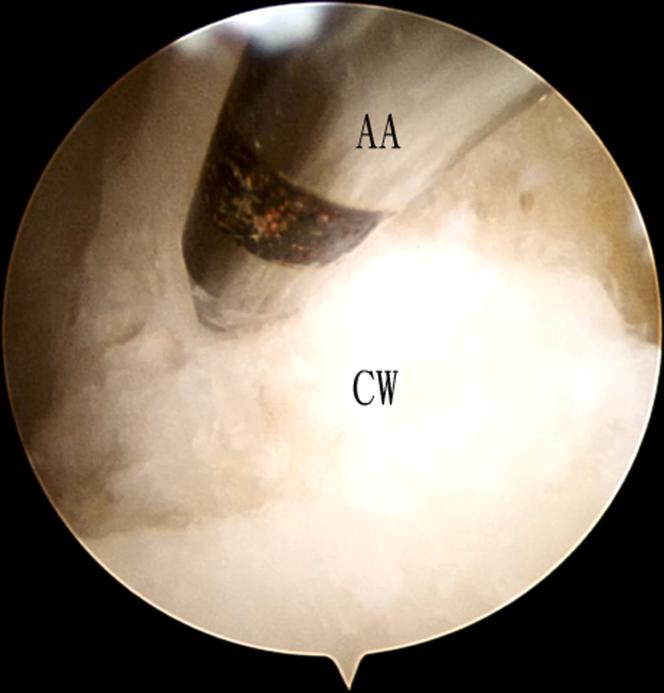

关节镜下治疗距骨体前半部分骨囊肿

Large talar bone cyst can cause pathologic fracture and damage to the articular cartilage, resulting in persistent swelling and pain of the subtalar joint and ankle joint. For a symptomatic cyst not responding to conservative treatment, surgery can be considered. Open debridement and bone grafting frequently require extensive soft-tissue dissection or even different types of malleolar osteotomy for proper access to the lesion. Arthroscopic treatment of talar bone cyst is a feasible alternative minimally invasive approach to reduce surgical trauma and eliminate the need for osteotomy. Bone cyst of the anterior part of the talar body can be debrided via a bone window of the talar neck, which is normally devoid of cartilage. The purpose of this Technical Note is to describe the technique of arthroscopic treatment of bone cyst of anterior half of the talar body. This minimally invasive approach does not disrupt the normal articular cartilage of the talar dome.

距骨大囊肿可导致病理性骨折并损害关节软骨,导致距下关节和踝关节持续肿胀和疼痛。对于对保守治疗无反应的有症状囊肿,可考虑手术治疗。开放清创和植骨通常需要广泛的软组织解剖,甚至不同类型的踝关节截骨术才能正确暴露病变。关节镜治疗距骨囊肿是一种可行的替代微创方法,可减少手术创伤并避免截骨术。距骨体前部的骨囊肿可通过距骨颈的骨窗进行清创,该骨窗通常没有软骨。本技术说明的目的是描述关节镜治疗距骨体前半部分骨囊肿的技术。这种微创方法不会破坏距骨穹窿的正常关节软骨。